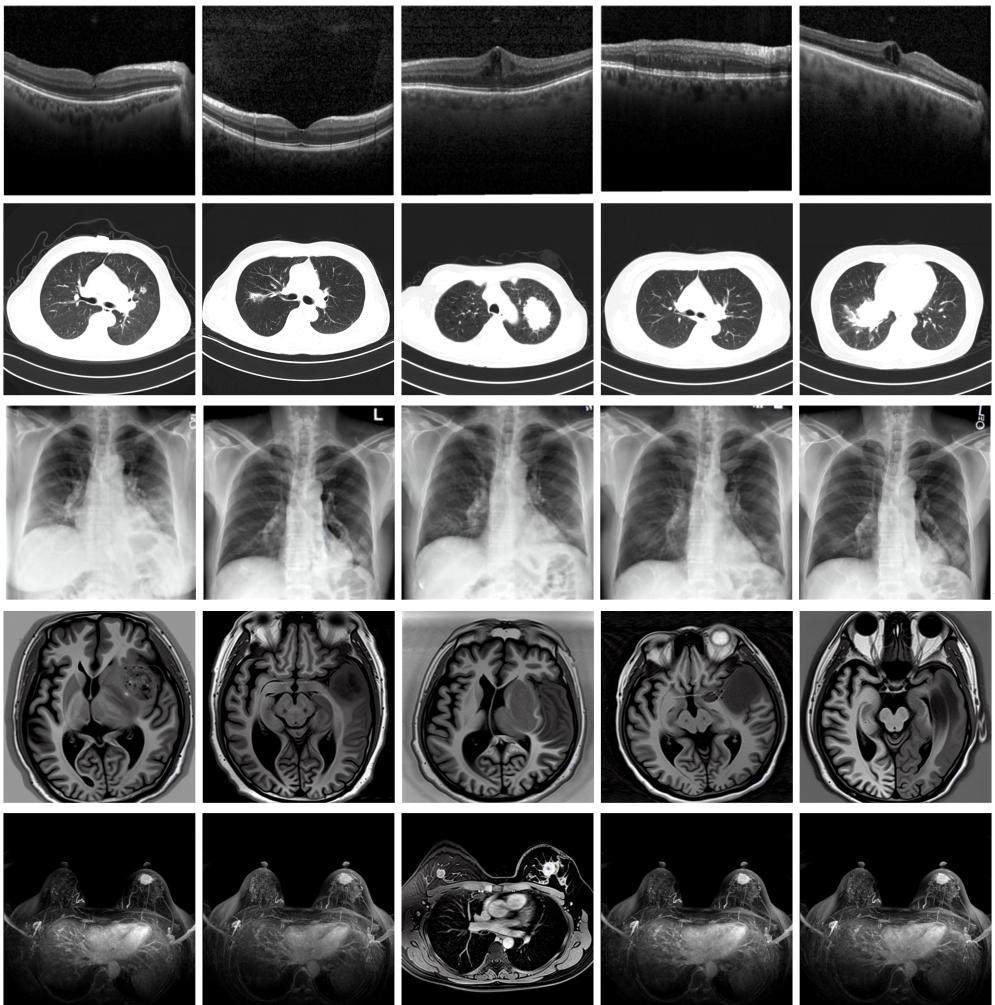

圖為由MINIM生成的高質(zhì)量醫(yī)學(xué)合成圖像(受訪者供圖)

“目前公開的醫(yī)學(xué)影像數(shù)據(jù)非常有限,我們建立的生成式模型有望解決訓(xùn)練數(shù)據(jù)不夠的問題。”北京大學(xué)未來技術(shù)學(xué)院助理研究員王勁卓說,研究團(tuán)隊(duì)利用多種器官在CT、X光、磁共振等不同成像方式下的高質(zhì)量影像文本配對(duì)數(shù)據(jù)進(jìn)行訓(xùn)練,最終生成海量的醫(yī)學(xué)合成影像,其在圖像特征、細(xì)節(jié)呈現(xiàn)等多方面都與真實(shí)醫(yī)學(xué)圖像高度一致。

實(shí)驗(yàn)結(jié)果顯示,MINIM生成的合成數(shù)據(jù)在醫(yī)生主觀評(píng)測(cè)指標(biāo)和多項(xiàng)客觀檢驗(yàn)標(biāo)準(zhǔn)方面達(dá)國(guó)際領(lǐng)先水平,在臨床應(yīng)用中具有重要參考價(jià)值。在真實(shí)數(shù)據(jù)基礎(chǔ)上,使用20倍合成數(shù)據(jù)在眼科、胸科、腦科和乳腺科的多個(gè)醫(yī)學(xué)任務(wù)準(zhǔn)確率平均可提升12%至17%。